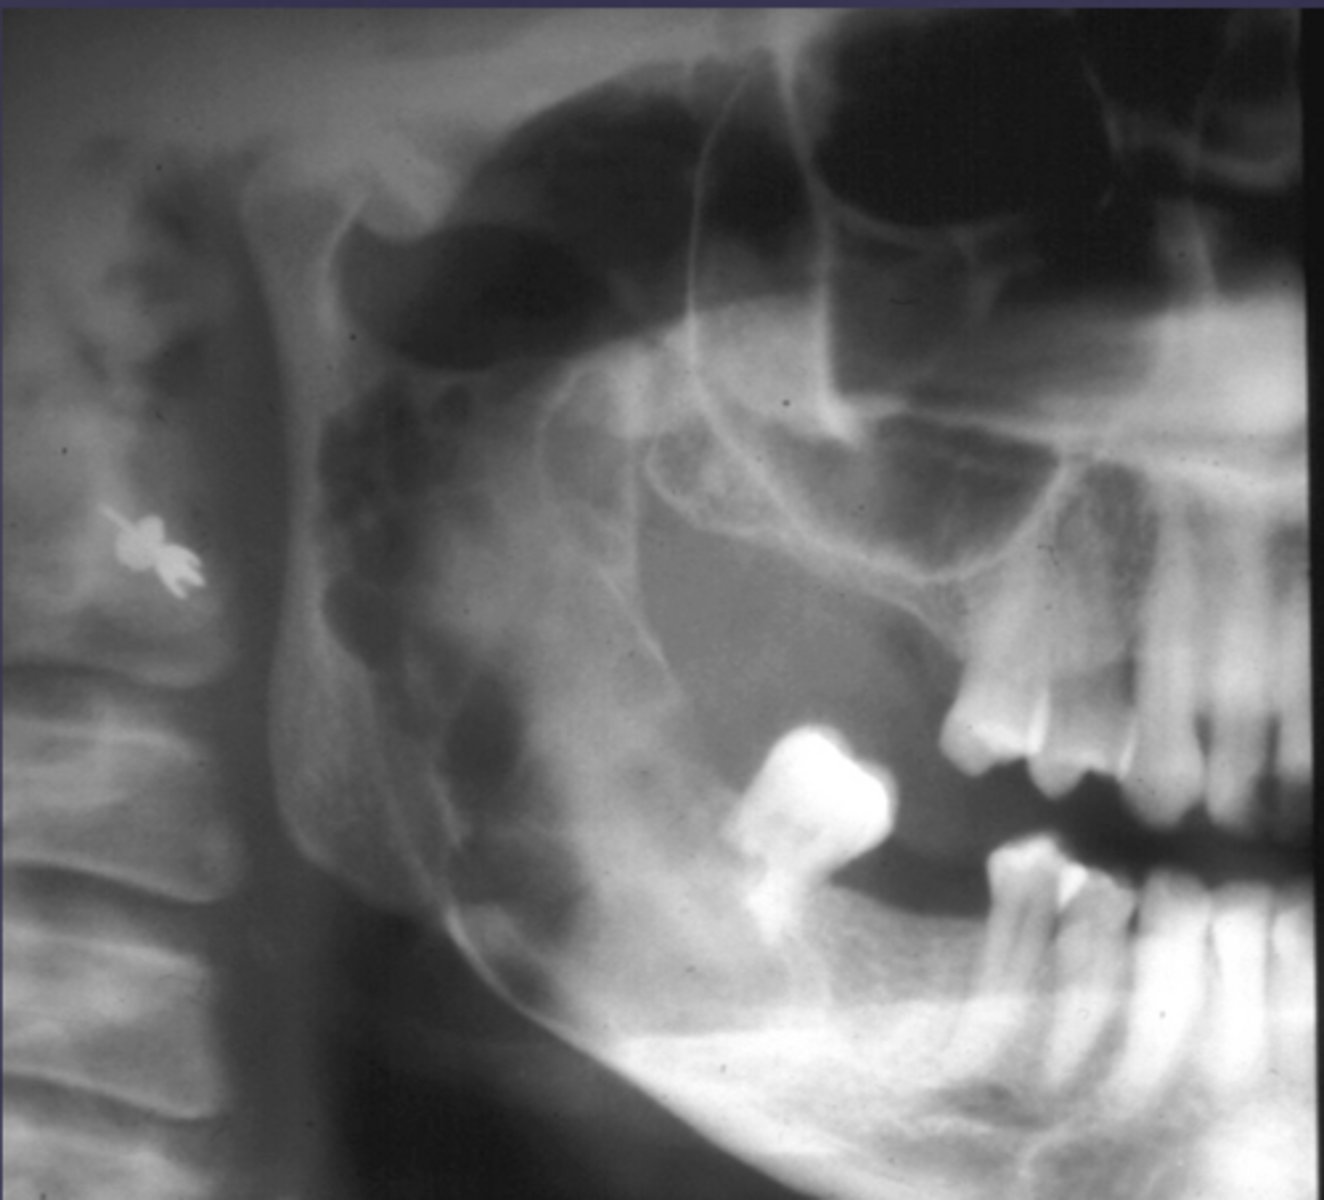

How would you describe the lesion?

- Defined corticated radiolucency associated with an impacted, displaced tooth

- Root resorption and teeth displacement also present along with thinning of the inferior mandibular cortex

- large calcifications noted just coronal to the impacted tooth

What category would this lesion be part of?

Benign

What would be a differential diagnosis for this lesion?

- Gorlins cyst

- Pindborg tumor

Calcified carotid atheromatous plaque

- Lamellar or concentric pattern

- Located below the IAN and in the area of submandibular salivary gland

Left submandibular sialolith